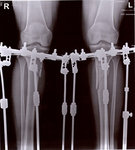

рентген в 90 дней.

Здравствуйте, Iskorka! По рентгену, сращение отличное, ждём на снятие аппаратов.